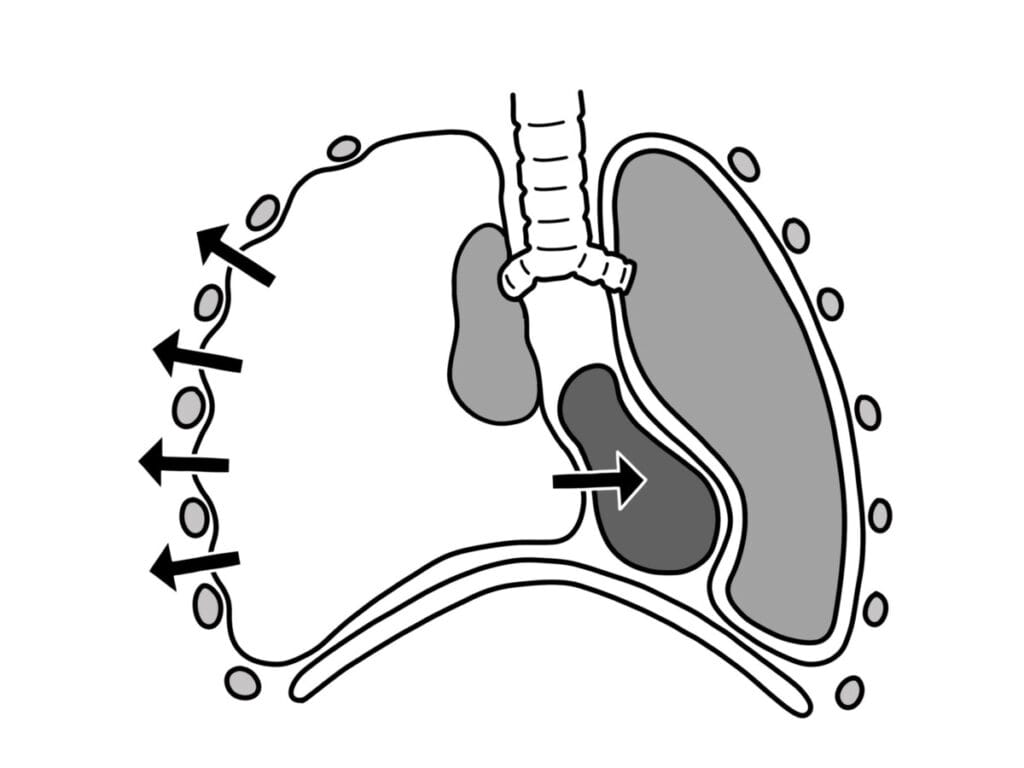

: 공기가 흉막강에 들어온 뒤 빠져나가지 못하고 계속 축적되어, 폐는 눌려서 허탈되고 심장 및 대혈관까지 압박하게 됩니다.

Tension Pneumothorax는 흉막강에 공기가 일방향으로 지속 유입되어 압력이 상승하면서 폐가 붕괴되고, 반대쪽으로 심장과 종격동이 밀리면서 생명을 위협하는 응급 질환입니다.

긴장성 기흉의 종격동 편위와 폐허탈 소견을 간결하게 설명한 그림이 있어 가져와봤습니다 🙂